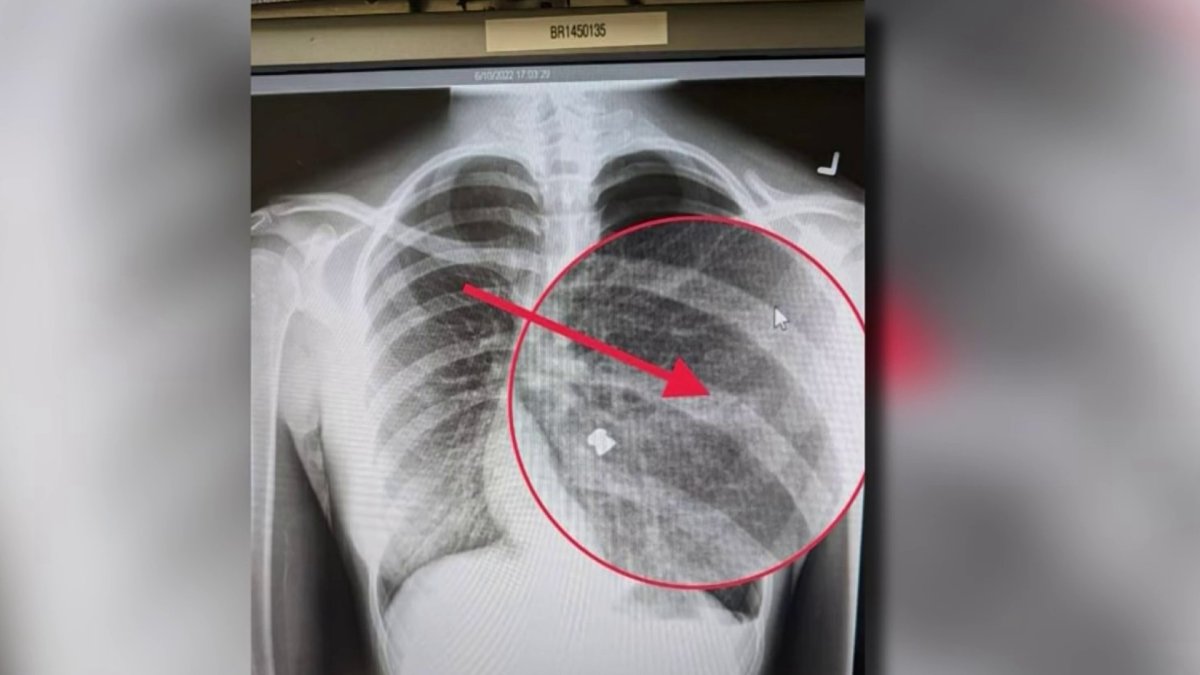

Bay Area teen's lung collapses after pellet gun attack Pellet Gun Shooter San Jose The incident caused internal bleeding and a collapsed lung, and sent the. Police arrested a man on tuesday suspected of a series of shootings from a pellet gun at seemingly random victims, which are. According to the san jose unified school district, a car drove by the campus in the. Police have arrested a man they suspect of using a. Pellet Gun Shooter San Jose.

'It almost killed me' San Jose teen suffers collapsed lung after Pellet Gun Shooter San Jose Police have arrested a man they suspect of using a pellet gun to shoot at least seven people, primarily girls and women, in san jose and campbell over the past six months. Police arrested a man on tuesday suspected of a series of shootings from a pellet gun at seemingly random victims, which are. The incident caused internal bleeding and. Pellet Gun Shooter San Jose.